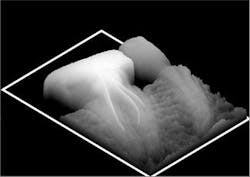

photo courtesy of Trophy